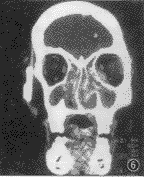

图6 鼻腔非霍奇金淋巴瘤,病灶呈弥漫浸润型,左眶、鼻甲、鼻中隔及右上颌窦内侧壁呈虫蚀样骨质吸收

3.骨质改变:8例(8/11)骨质破坏较不明显,呈筛孔状或虫蚀样骨质吸收(图 6),见于鼻中隔鼻甲、筛窦间隔及上颌窦内侧壁。3例见小范围较明显的骨质破坏缺损,于鼻中隔软骨部使鼻腔前端溶蚀成 1个空腔;另于眼眶内下壁及上颌窦后外侧壁(图 2)的相应部位见外侵的软组织影,但其宽度远大于骨质缺损范围。